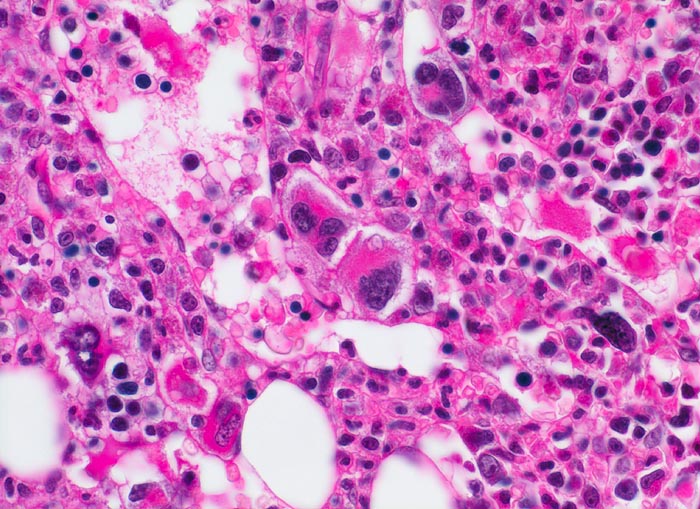

• Vermehrung von atypischen, in Gruppen liegenden Megakaryozyten mit abnorm lobulierten Kernen.

• Nacktkernige (zytoplasmaarme) und vergrösserte Megakaryozyten.

• Dilatierte Sinusoide mit intrasinusoidaler Blutbildung.

• Hyperplastische ausreifende Myelopoese.

• Hypoplastische Erythropoese.